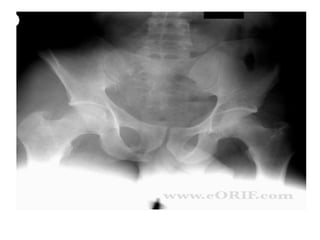

Pelvic Ring Injuries

• Exsanguinating haemorrhage associated with

pelvic fracture

• Conditions where haemorrhage can be

expected, when there is pelvic injury :

-Posterior pelvic ring injuries

-Anterior-posterior compression type III injuries,

lateral compression injuries

-Pelvic fracture in patients over 55 years old

Pelvic Ring Injuries •Exsanguinating haemorrhage associated with pelvic fracture • Conditions where haemorrhage can be expected, when there is pelvic injury : -Posterior pelvic ring injuries -Anterior-posterior compression type III injuries, lateral compression injuries -Pelvic fracture in patients over 55 years old